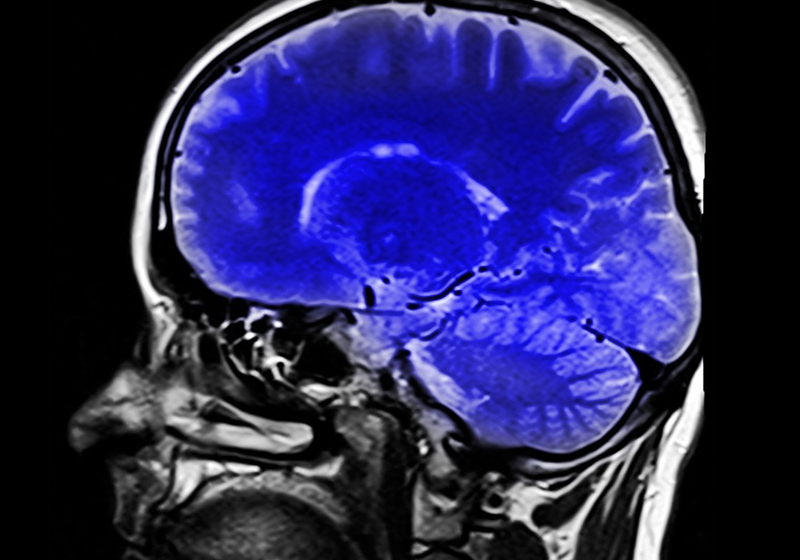

Novo exame detecta AVC e pode antecipar tratamento

Identificação mais precisa e diagnóstico antecipado do AVC.

Uma nova técnica feita por ressonância, desenvolvida por cientistas da Universidade de Oxford, na Grã-Bretanha, é capaz de prever com antecedência o risco de acidente cerebral.

Os periódicos científicos JACC e PLOS ONE disseram que a ressonância é capaz de rastrear as carótidas, artérias que ligam ambos os lados do pescoço ao cérebro, em busca de possíveis placas de colesterol.

Essas são as placas que podem causar o acidente vascular cerebral.